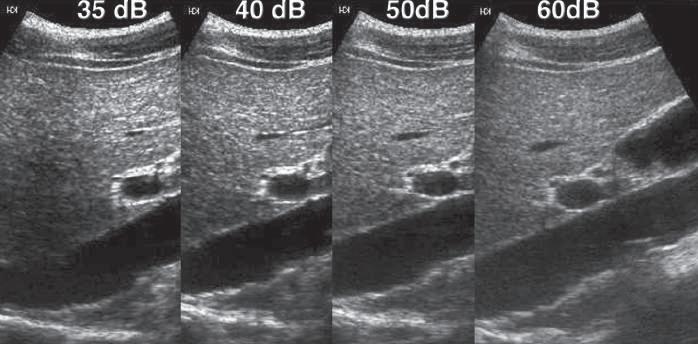

Another important function of the receiver is the compression of the wide range of amplitudes returning to the transducer into a range that can be displayed to the user. The ratio of the highest to the lowest amplitudes that can be displayed may be expressed in decibels and is referred to as the dynamic range. In a typical clinical application, the range of reflected signals may vary by a factor of as much as 1 : 1012, resulting in a dynamic range of up to 120 dB. Although the amplifiers used in ultrasound machines are capable of handling this range of voltages, gray-scale displays are limited to display a signal intensity range of only 35 to 40 dB. Compression and remapping of the data are required to adapt the dynamic range of the backscattered signal intensity to the dynamic range of the display (Fig. 1.11). Compression is performed in the receiver by selective amplification of weaker signals. Additional manual postprocessing controls permit the user to map selectively the returning signal to the display. These controls affect the brightness of different echo levels in the image and therefore determine the image contrast.

FIG. 1.11 Dynamic Range. The ultrasound receiver must compress the wide range of amplitudes returning to the transducer into a range that can be displayed to the user. Here, compression and remapping of the data to display dynamic ranges of 35, 40, 50, and 60 dB are shown. The widest dynamic range shown (60 dB) permits the best differentiation of subtle differences in echo intensity and is preferred for most imaging applications. The narrower ranges increase conspicuity of larger echo differences.

Because B-mode display relates the strength of a backscattered signal to a brightness level on the display device, it is important that the operator understand how the amplitude information in the ultrasound signal is translated into a brightness scale in the image display. Each ultrasound manufacturer offers several options

for the way the dynamic range of the target is compressed for display, as well as the transfer function that assigns a given signal amplitude to a shade of gray. Although these technical details vary among machines, the way the operator uses them may greatly affect the clinical value of the final image. In general, it is desirable to display as wide a dynamic range as possible, to identify subtle differences in tissue echogenicity (see Fig. 1.11).